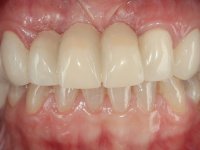

The patient did not like her smile, said that she had "very artificial looking teeth".

Female patient, 43 years old non-smoker. After a clinical and imaging examination, the patient presented teeth 1.7 / 1.4 / 1.3 / 2.2 / 2.3 / 2.4 / 2.6 with endodontic treatment in the upper jaw, showing absence of teeth 1.6 / 1.5 / 1.2 / 1.1 /2.1 and 2.5, and was rehabilitated with a 10-element monobloc metal-ceramic bridge. The anterior maxilla presented extensive vertical and vestibular bone reabsorption. In the lower jaw, two implants were placed at the site of teeth 4.6 and 4.5 rehabilitated with a metal-ceramic bridge. Teeth 3.6 and 3.7, with endodontic treatment, were rehabilitated with intra-radicular posts and a two-element metal-ceramic bridge. The antero-inferior teeth presented class III and IV resin restorations. Tooth 3.5 was absent. The patient had a vertical dimension of occlusion reduction, accompanied by accentuated dental wear and some ceramic fractures. Good oral hygiene.